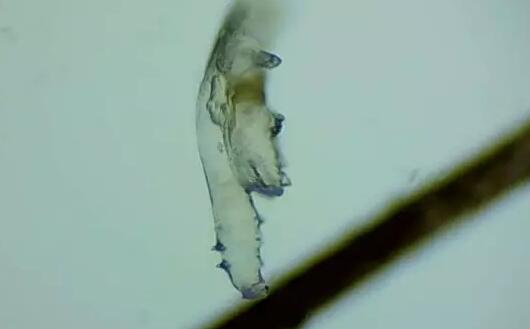

随着年龄增长,眼睛寄生有蠕形螨的几率也会逐渐增加,60、70岁左右的人群感染螨虫的几率更是接近99%。蠕形螨会引起蠕形螨性睑缘炎,患者会出现眼痒、异物感、眼干、睑缘充血、鳞屑、睫毛根部袖套状分泌物及睫毛脱落等典型表现,严重者可并发结膜及角膜病变。